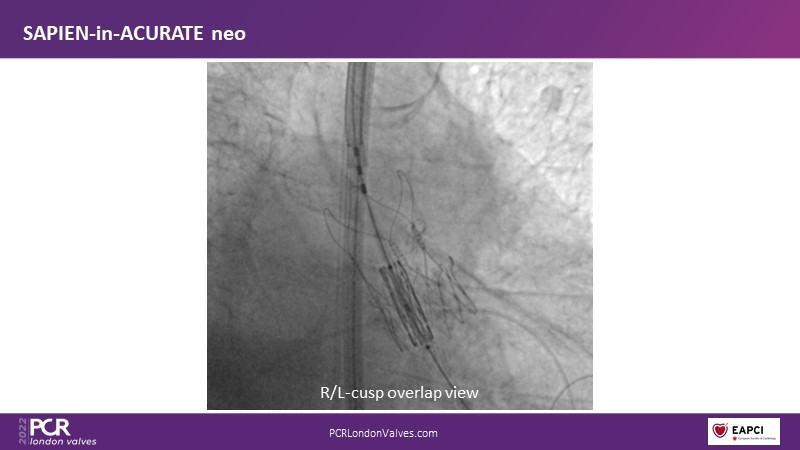

TAVI-in-TAVI - A road map for successful lifetime management

Join a team of experts that guide you through the basics of TAVI-in-TAVI, the procedural planning and techniques of implantation, followed by case examples with different index prostheses.